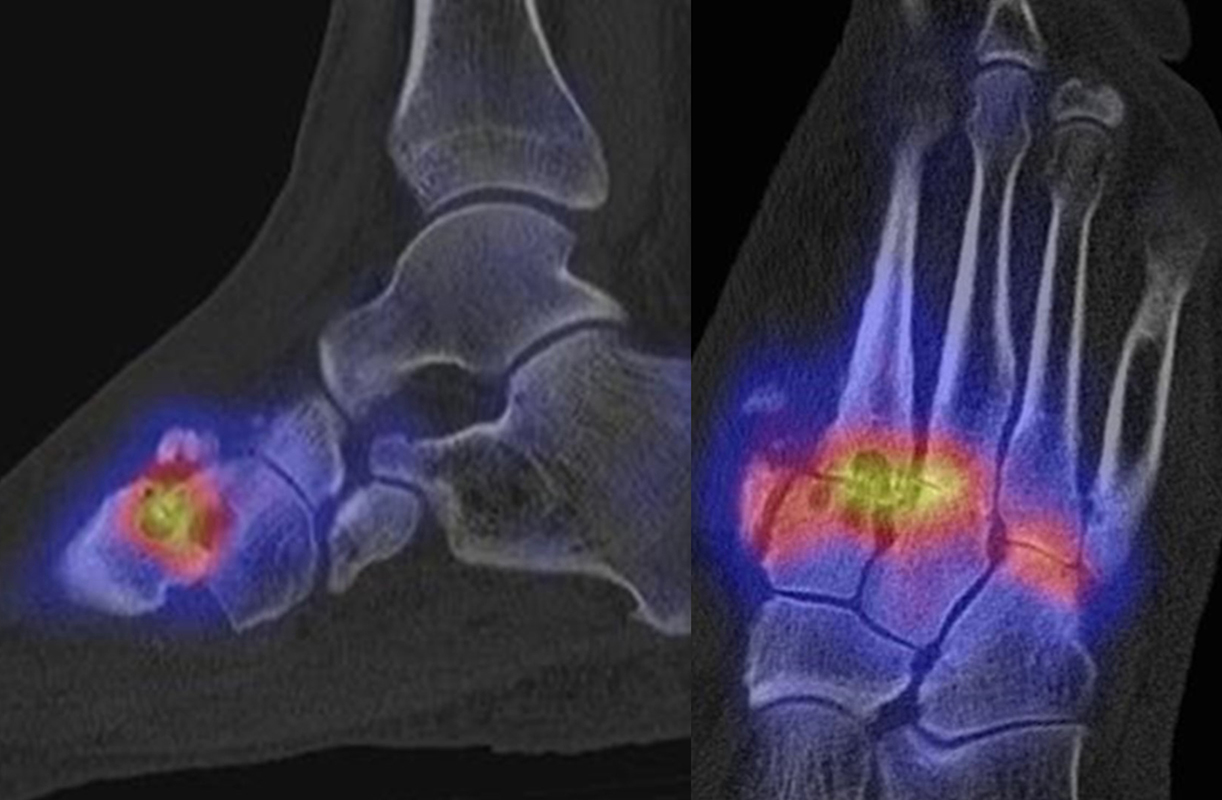

Abbildung 3.1.

Beispiel für eine symptomatische Arthrose im Gelenk zwischen lateralem Sesambein und Köpfchen von Os metatarsale I.

Bekannte Gicht mit Polyarthralgien. Am rechten Großzehengrundgelenk lateral in der Grundphalanx entzündliche Erosionen.

Gichtarthritis mit Osteolysen und flauen Verkalkungen in den periartikulären Weichteilen/Gelenkkapsel.